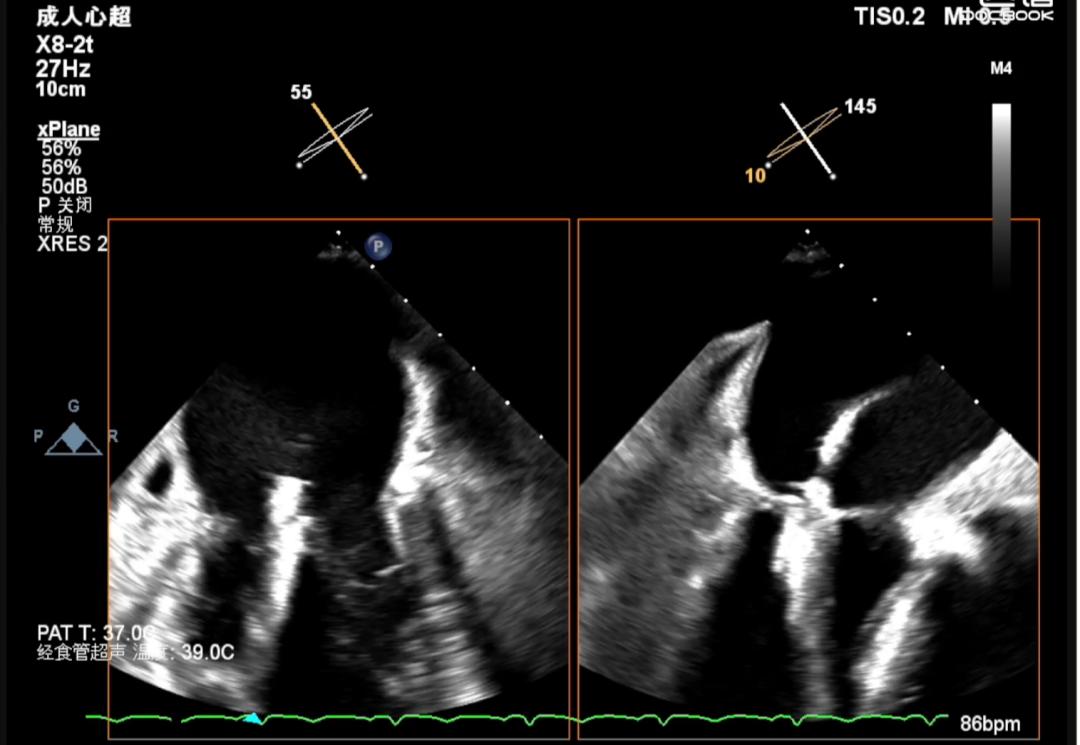

全麻状态下陈魁主任手术团队(图四)经右侧股静脉穿刺,通过MitraClip®独特的三层双调弯设计,经房间隔穿刺顺利将导管送入左心房和左心室,到达二尖瓣膜目标位置调整角度抓取瓣叶(图五)。随后,术者精准对位释放MitraClip®夹合器,准确捕获并固定(图六),“缘对缘”技术使二尖瓣由大的单孔变成小的双孔,位置精确(图七)控制返流且无瓣口狭窄(图八),血流动力学明显改善,手术取得圆满成功。

图七(MitraClip稳定于病变位置)

图八(评估夹合后二尖瓣无狭窄)